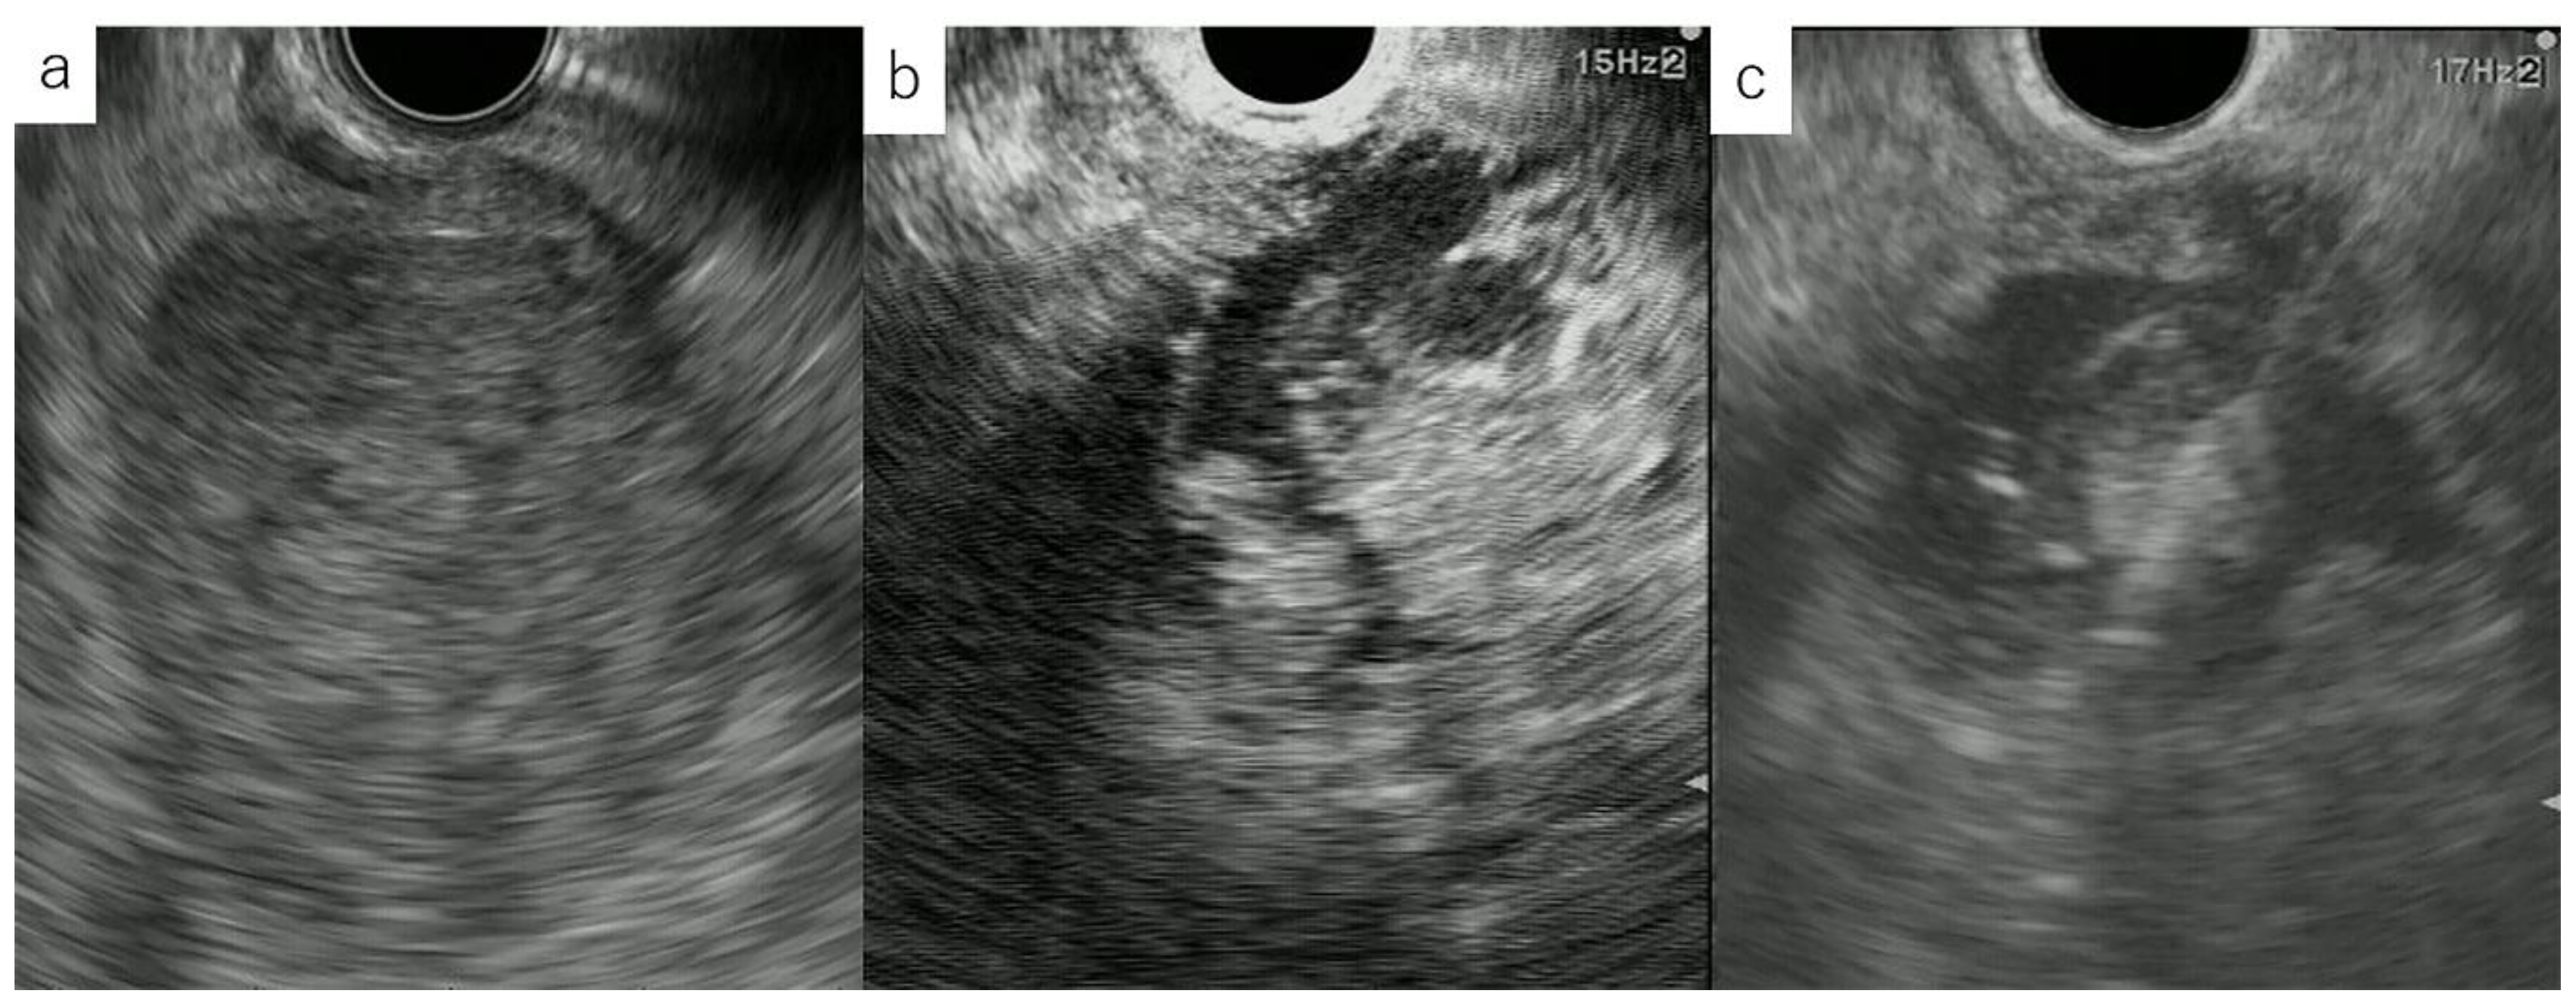

2.2. CH-EUS

- The echo image of CH-EUS should be lowered to a level at which almost no tissue signal is detected.

- The focus point is set to the lowest point of the lesion.

- The fundamental B-mode image is simultaneously depicted as a monitor image in order to facilitate orientation during contrast enhancement.

- Because attenuation makes it more difficult to observe deep lesions than Fundamental B mode, the area where the lesions are observed in close proximity to each other should be searched before contrast enhancement.